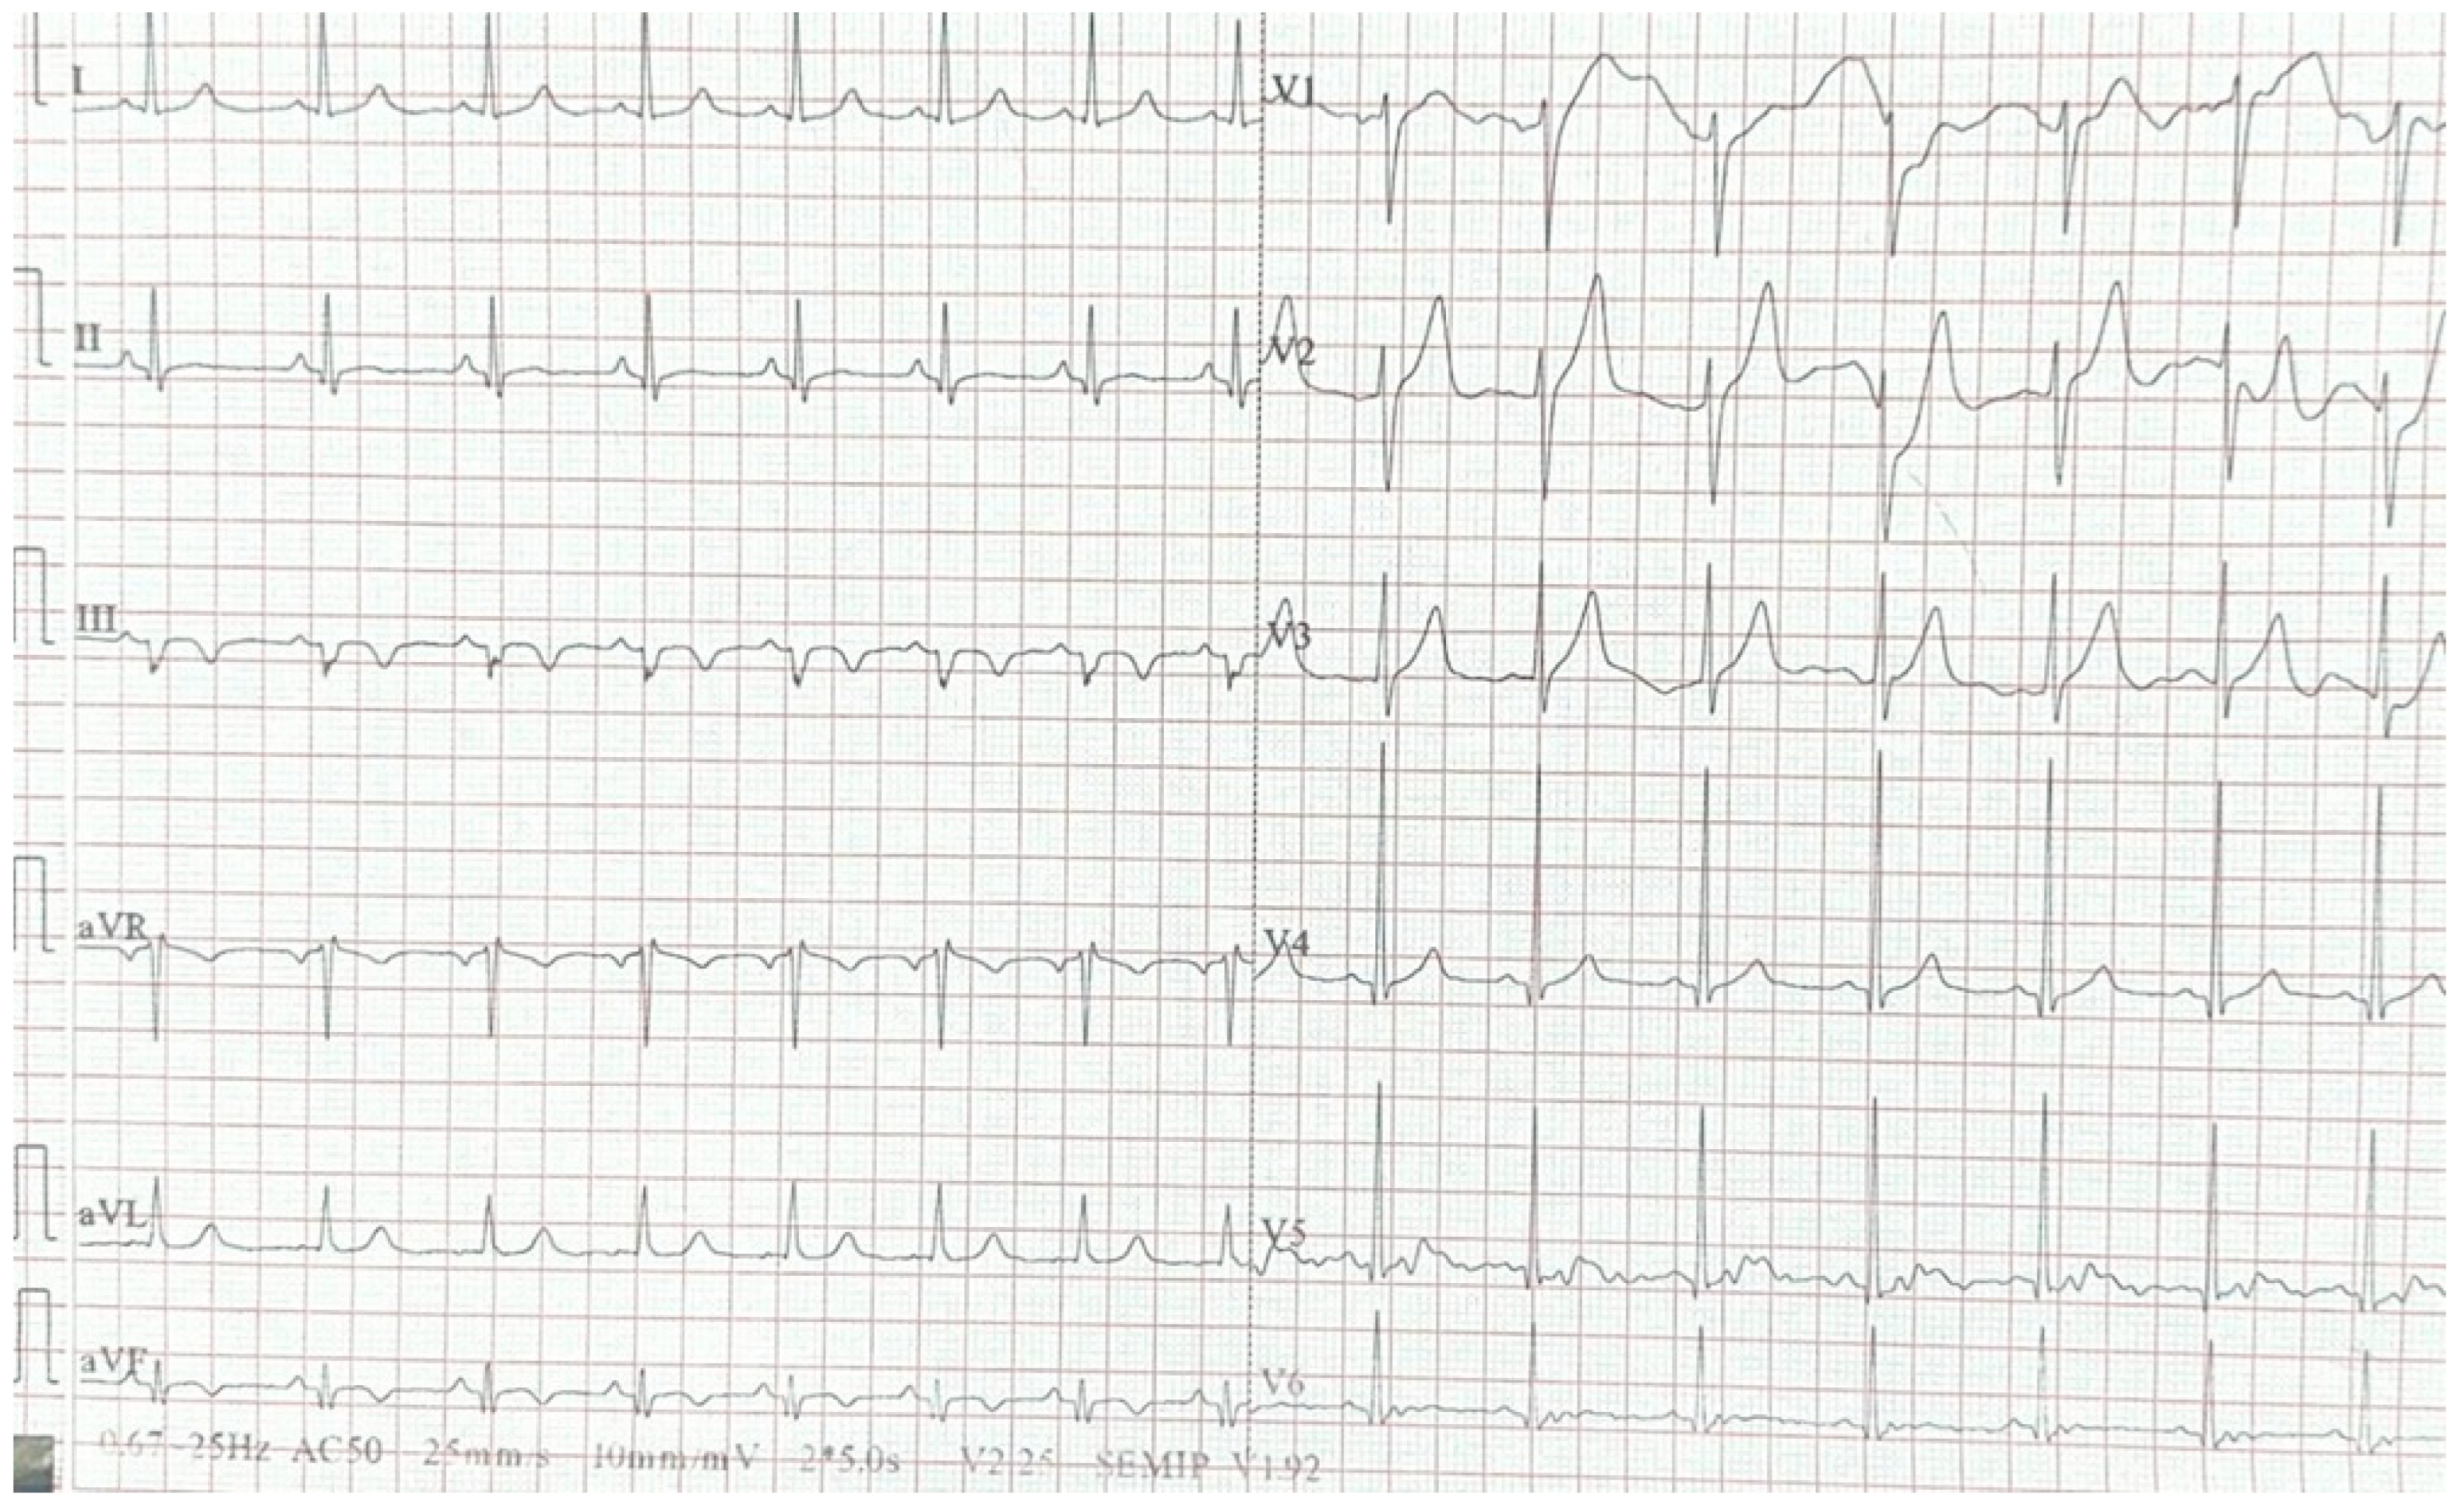

2. Case Report